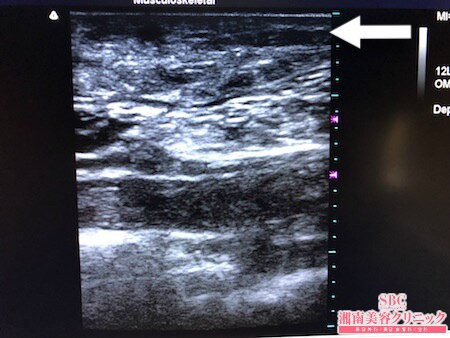

No.235809【脂肪吸引】【動画あり】湘南美容外科脂肪吸引最高責任者である竹田先生による脂肪吸引のフォトギャラリー!近所の美味しいパン屋さんのパンを食べ続けて1年で12kg太った患者様のおなかの皮下脂肪を根こそぐ!術中3Dタッチビュー・下腹部